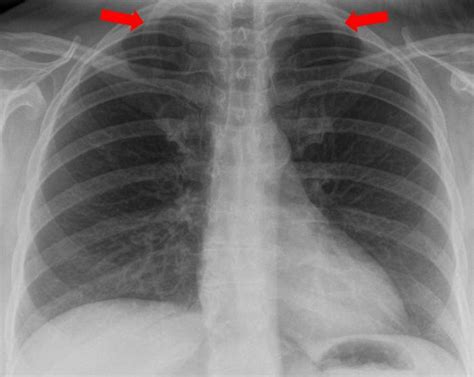

Im röntgen zeigt sich nur bei fulminanten verläufen ein vergrößertes herz.